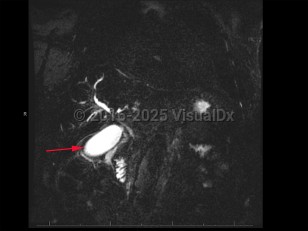

Cholangiocarcinoma refers to biliary tree malignancies, primarily adenocarcinomas, of epithelial cell origin. They are typically categorized as intrahepatic, perihilar, or distal.

Cirrhosis, hepatitis B, hepatitis C, primary sclerosing cholangitis, and hepatobiliary flukes are known risk factors for cholangiocarcinoma. However, most cholangiocarcinomas develop in patients with no identifiable risk factors. It is a rare childhood malignancy. Incidence is highest in Hispanic and Asian populations.

Overall prognosis is poor, as many patients present with advanced disease. Early detection of tumors that can be resected surgically portends the most favorable prognosis. Chemotherapy can slow disease progression but is rarely curative.